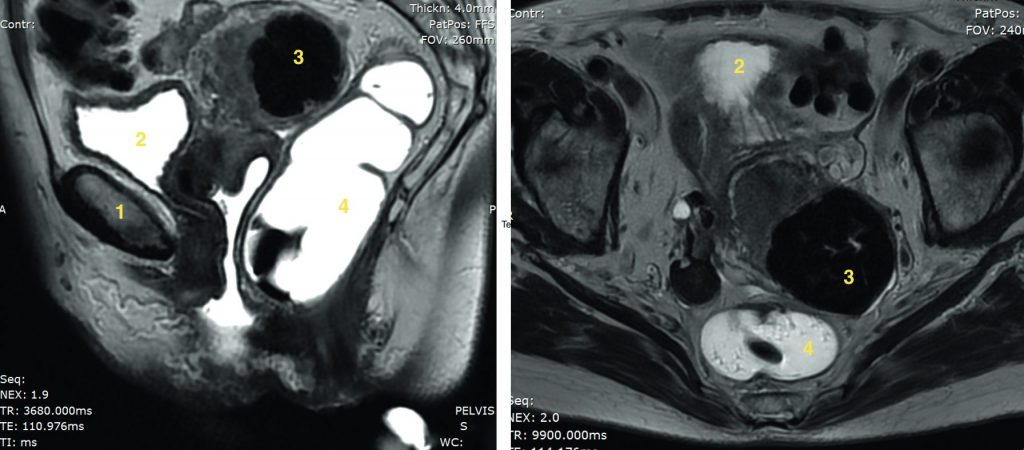

Fig. 20.3 Coupe axiale (A) et coronale (B) d’IRM pelvienne en séquence T2 chez une patiente de 28 ans présentant des douleurs pelviennes latéralisée à droite.

On retrouve une formation uniloculaire pure développée aux dépens de l’ovaire droit de paroi fine, en franc hypersignal T2 liquidien, sans végétation ni portion tissulaire, faisant évoquer fortement un kyste fonctionnel de l’ovaire.

Source : CERF, CNEBMN, 2022.

Le scanner ne présente plus d’indication pour la caractérisation d’une masse pelvienne, en dehors d’une suspicion échographique de tératome (figures 20.4 et 20.5). Il reste utile dans le contexte de l’urgence, en particulier pour éliminer une torsion annexielle surajoutée ou dans un contexte septique abdominopelvien ou dans le bilan d’extension d’une masse ovarienne suspecte.

Fig. 20.4 Coupe axiale d’échographie pelvienne centrée sur un kyste ovarien droit mixte (liquidien et solide).

1. Portion liquidienne anéchogène. 2. Portion solide. 3. Calcification hyperéchogène atténuante.

Fig. 20.5 Coupe axiale de scanner pelvien sans injection centrée sur un kyste ovarien droit mixte (liquidien et solide), même patiente que la figure 25.4.

1. Portion liquidienne. 2. Portion hypodense graisseuse. 3. Calcification. 4. Paroi du kyste.